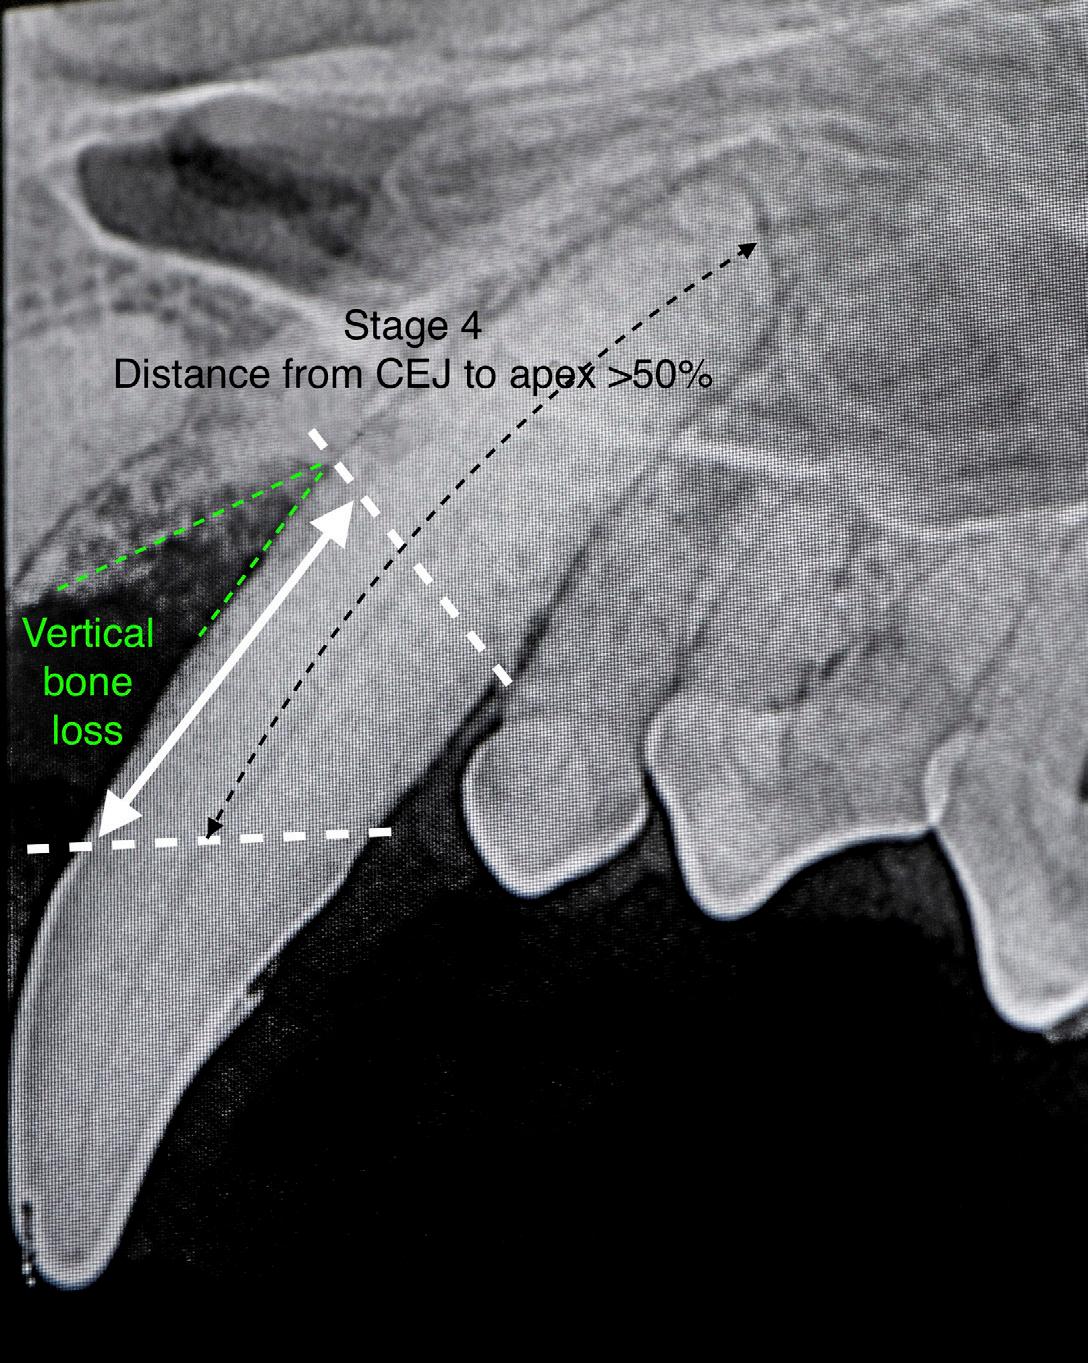

Periodontal disease can be classified from stages 1 to 4 based on the severity of radiographic and clinical findings. The toothsupporting bone height in periodontal disease decreases as inflammation and infection increases and bone is resorbed. Around 40% of the bone’s thickness must be destroyed before it is detected radiographically. Distribution of bone loss is classified as either localized or generalized, depending on the number of areas affected. Specific areas of bone loss may be classified as horizontal (perpendicular to the tooth) or vertical (angular along the side of the root).

Figure 1: Periodontal anatomy. Image courtesy of Dr. Jan Bellows. Figure 2: Vertical bone loss typical in moderate periodontal disease. Image courtesy of Dr. Jan Bellows.

Stage

3 - Moderate Periodontitis

This is diagnosed when 25-50% of attachment loss occurs. The direction of bone loss may be horizontal or vertical (angular).

4 - Advanced Periodontal Disease

This is typified by deep pockets and/or marked gingival recession, tooth mobility, gingival bleeding, and purulent discharge. Attachment loss is greater than 50% of the root length.